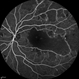

- capillary closure, macular infarction

- Wide-field FA image of the left eye of a 28-year-old woman with idiopathic occlusive retinal vasculitis 6 months after the onset.